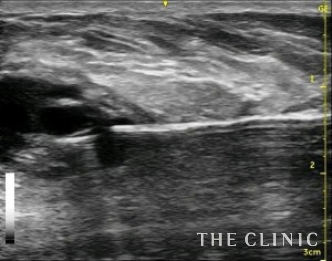

今回は5cm以上の充実性で、被膜が厚いしこりのため乳輪切開の摘出をすすめましたが、傷を作りたくないという希望があり、ベイザーリポによる治療を選択しました。術前のエコー像です。ベイザーで壊死脂肪を崩して吸引します。